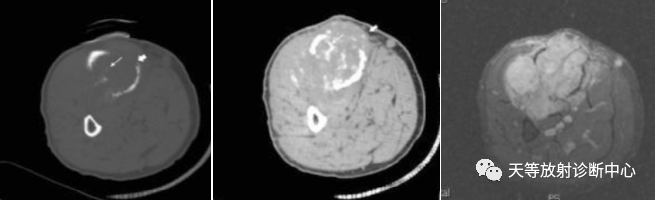

病例4:软骨肉瘤。左胫骨中上段局限性骨质破坏影,CT 横断平扫(骨窗)显示病变骨皮质的破坏(白箭头)、骨内软骨基质成分(白箭),CT软组织窗能显示骨内软骨成分的钙化(白箭)、以及骨外的软组织肿瘤,MRI显示骨皮质破坏的情况,以及骨外软组织肿瘤。

注:病例4来源:冯 刚,陈 雷,何 晓.等。去分化软骨肉瘤 45 例 DR、CT、MRI 影像特征分析[J].现代医用影像学.2020,29(3):428-430.